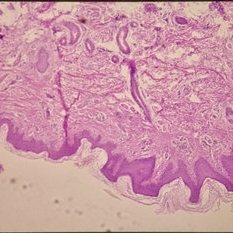

Histopathology of Linear Sebaceous Nevus Syndrome

Histopathology of Linear Sebaceous Nevus Syndrome

Feb 20 2015 by H. Michael Lambert, MD

Histopathology of linear sebaceous nevus syndrome.

Condition/keywords: histopathology, linear nevus sebaceous syndrome